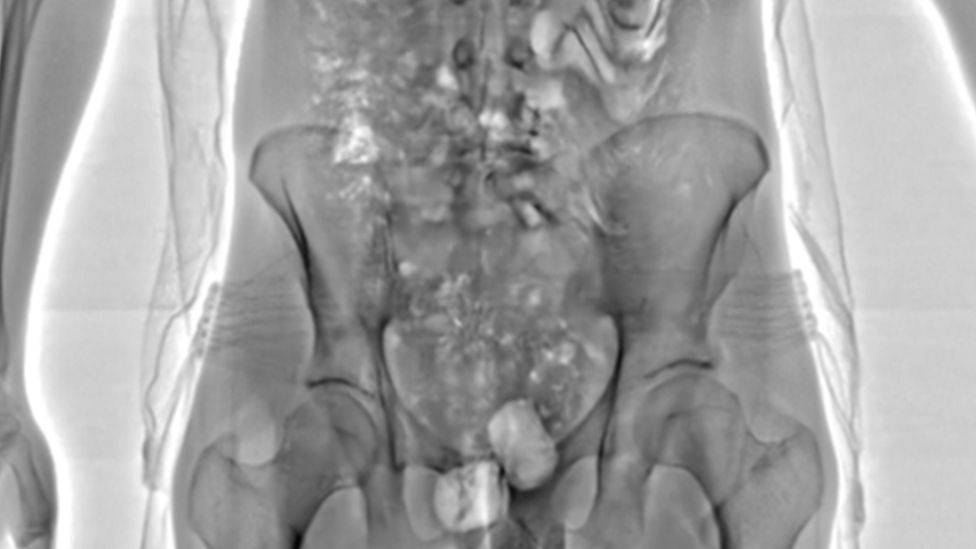

В 16 самых проблемных исправительных учреждениях Великобритании установлены сканеры, которые просвечивают человека и моментально показывают, прячет ли он оружие, мобильный телефон или наркотики. Весь проект оценивается в £28 млн ($38,1 млн). В 2018 году подобное оборудование в тестовом режиме работало в десяти английских тюрьмах и вдвое снизило положительные тесты на наркотики, на 16% случаи нападения.

Тюремный сканер выявил контрабанду наркотиков в желудке одного из осужденных, Великобритания